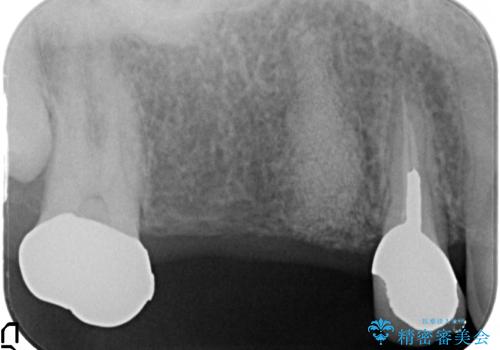

- 右上のブリッジでものを咬むと違和感があり、歯茎に膿の出口もできているので診て欲しいといらっしゃった方の症例です。

右上の567ブリッジを外したところ、右上5は歯根破折により保存不可能だったため、右上56部にインプラントを埋入し欠損補綴を行いました。

また右上5部に関しては抜歯時に歯槽堤保存術(抜歯窩に人工骨の填入を行う手術)を行い、骨の欠損を最小限に止めています。